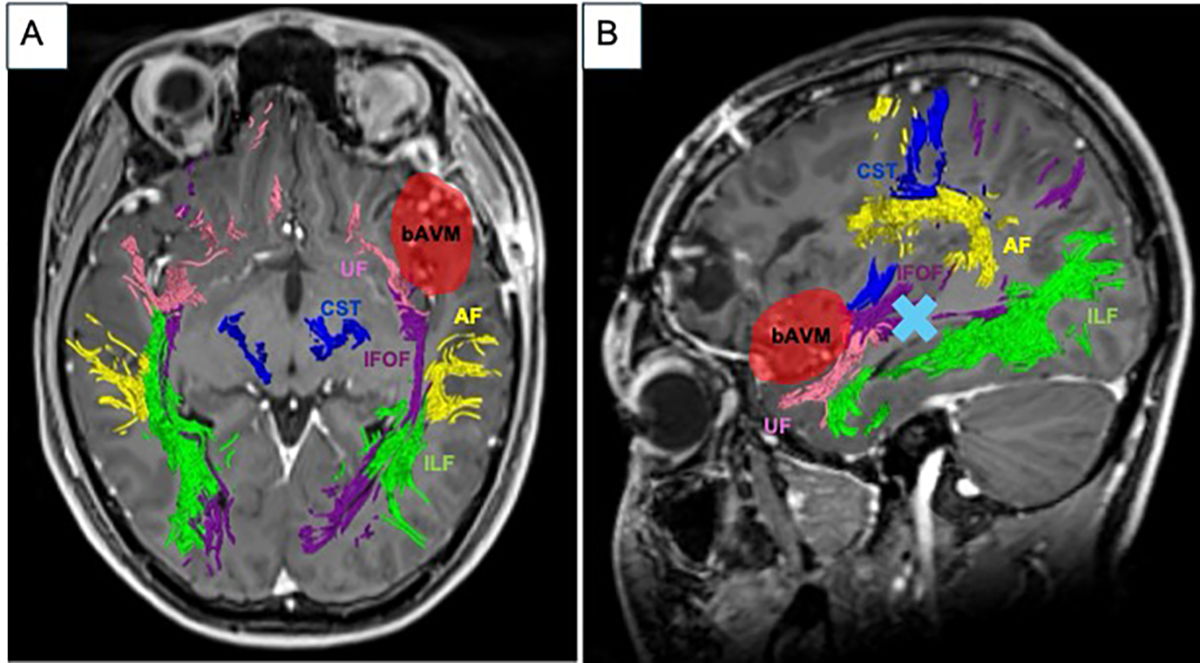

2. Case Report